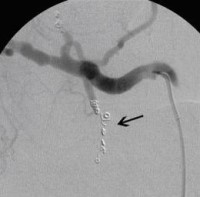

Vor perkutaner transluminaler Angioplastie (PTA) der Unterschenkelgefäße

(Bild 3 von 4)

Nach perkutaner transluminaler Angioplastie (PTA) der Unterschenkelgefäße

(Bild 4 von 4)